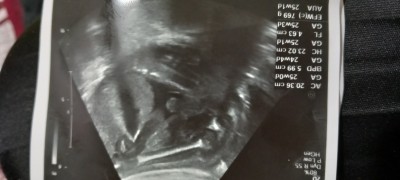

Kizlar Bi kızım vardı içten öyle Bi dua ediyodumki allahim kız evlat verdin bide oğlan nasip et diye Rabbım öyle büyükki geçen ay Dr erkek ama tan net değil kızda olabilir dedi ve bugün bana gösterdi erkek olduğunu ve oglusumun pipisini net gördük bugün çok mutluyum Rabbım çocuğu olmayana nasip etsin inşallah Rabbım herkese iki meyvedende nasip etsin

image